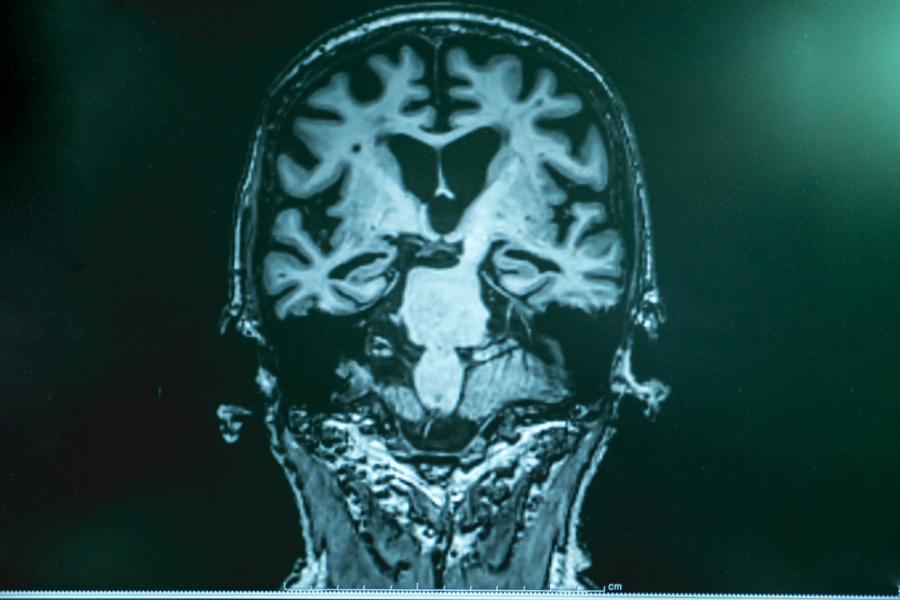

Преди всичко това е първото лекарство, насочено срещу механизма на самата болест, наличието на бета-амилоидни плаки в мозъка, а не само срещу симптомите, причинени от болестта, като страх и безсъние.

Цената на медикамента ще е между 30 000 и 50 000 долара на година, като възстановяването на сумата ще зависи от здравната застраховка на пациента. Лекарството се прилага интравенозно веднъж на четири седмици. В основата на медикамента е съединение, наречено адуканумаб. Това са моноклонални антитела, които изчистват клъстърите от бета-амилоид от мозъка. Други експериментални медикаменти са правили същото преди, но при тях няма разлика в способността на пациента да мисли, да се грижи за себе си или да живее независимо.